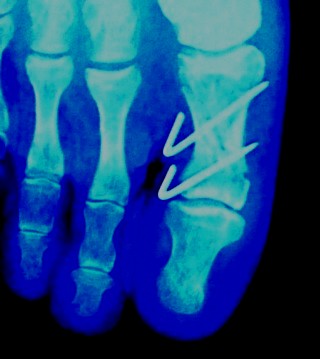

DR650で事故ってしまいました